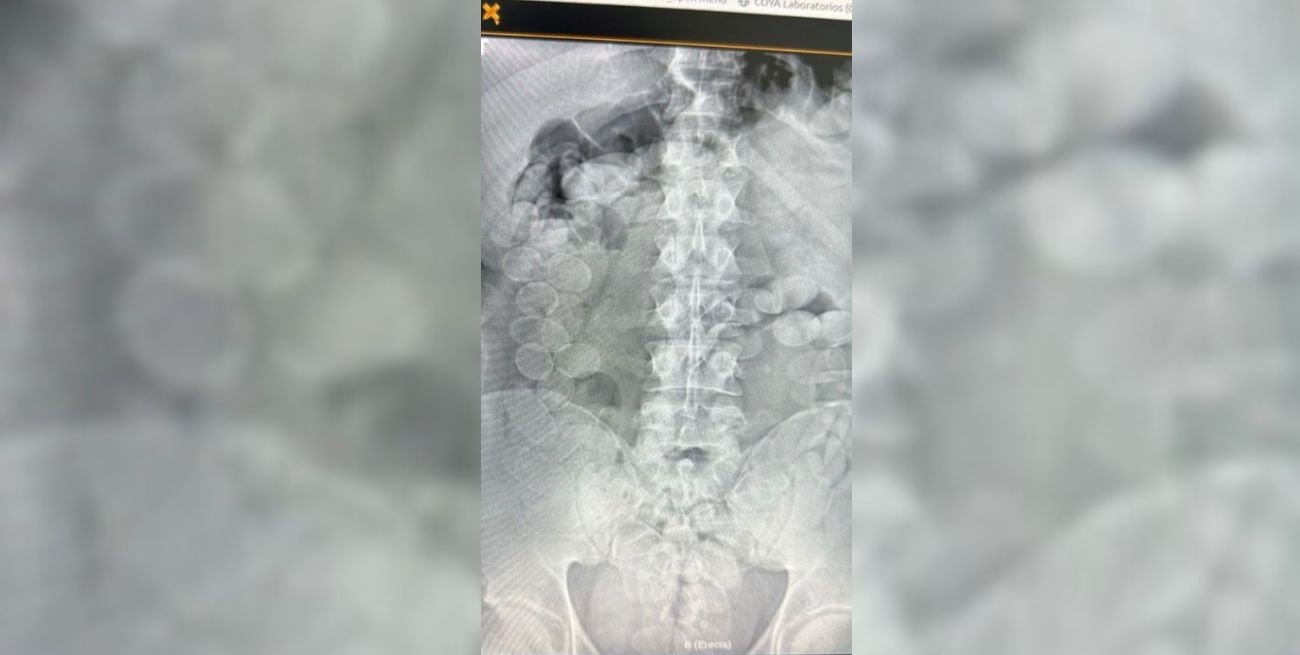

El personal médico confirmó rápidamente las sospechas. Las radiografías mostraron la presencia de decenas de cuerpos extraños en los estómagos de ambos hombres. Con supervisión médica y en presencia de Gendarmería, comenzó el procedimiento para que expulsaran las cápsulas de manera controlada.

La cifra final impactó incluso a los propios investigadores: cada uno llevaba 90 cápsulas de cocaína, lo que totalizó 180 bochas. Los especialistas subrayaron que una sola ruptura podría haber sido fatal, un riesgo que enfrentan quienes se prestan a actuar como “mulas”.